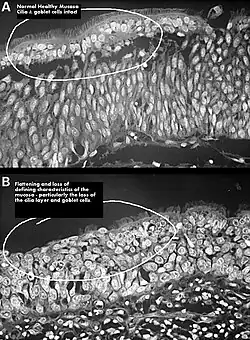

One possible cause may be changes to the nasal mucous membrane and to the nerve endings in the mucosa resulting from chronic changes to the temperature and humidity of the air flowing inside the nose, caused in turn by removal or reduction of the turbinates.[3][7] The TRPM8 receptor, responsible for the sensation of nasal openness (patency), is activated by high-speed airflow, which cools the nasal lining through evaporation. This cooling triggers signals to the brain, making breathing feel easier. Nasal passage enlargement alters airflow, reducing turbulence and mucosal cooling which results in reduced sensation of airflow. Studies confirm that without the inferior turbinate, air conditioning in the nose is less effective.[7]